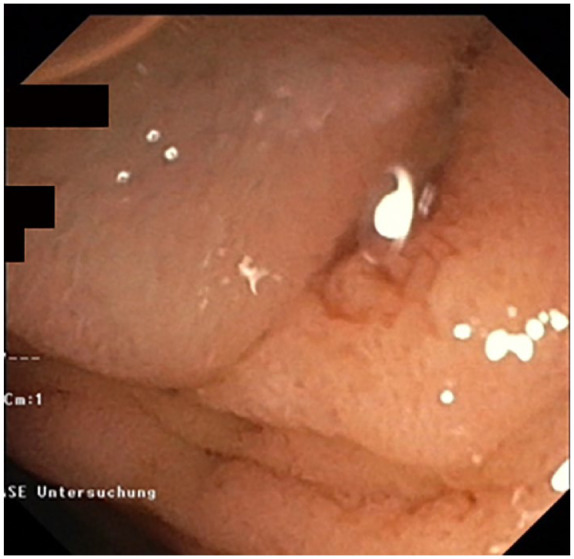

After failed biliary cannulation via standard endoscopic retrograde cholangiography approach, endoscopic-ultrasound-based rendezvous-endoscopic retrograde cholangiography (EUS-RV-ERC) is a valid alternative. One of the challenging factors in this setting is the management of the guidewire. Here, we propose a method, where a slim endoscope is used to stabilize the guidewire and optimize wire manipulation in a patient who underwent EUS-RV-ERC via a transgastric approach. This was executed in a patient suffering from severe alcoholic pancreatitis presented with a severely narrowed duodenum due to extrinsic compression and inflammation in the setting of cholangitis Tokyo Grade III.

Abstract Image